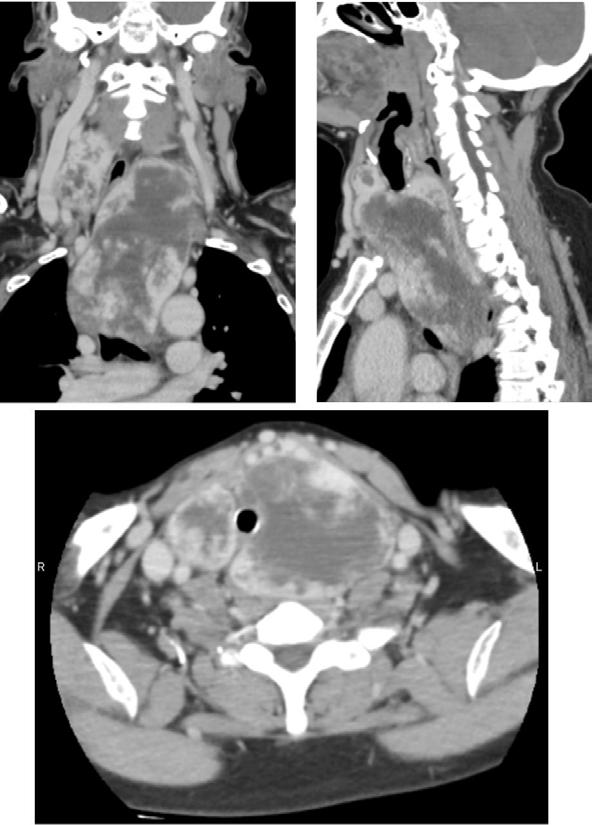

Médicos del Hospital Nacional

Daniel Alcides Carrión lograron tratar un complejo caso de bocio gigante, una enfermedad que afecta la glándula tiroides y puede comprometer funciones vitales.

El Hospital Nacional Daniel Alcides Carrión del Callao ha logrado un importante avance en la atención de enfermedades endocrinas al tratar con éxito a una paciente diagnosticada con bocio gigante, una afección que provoca el crecimiento anormal de la glándula tiroides y puede generar complicaciones respiratorias y cardiovasculares.

La paciente, identificada como Consuelo Rujel Sanjinés, se encuentra hospitalizada y en proceso de recuperación tras la intervención médica. El equipo de especialistas del hospital asumió el desafío destacando el compromiso del personal de salud con la atención de enfermedades de alta complejidad.

poco FrecUente

El bocio gigante es una patología poco frecuente que puede generar serias

dificultades para respirar, tragar y hablar, debido a la compresión de la tráquea y otros órganos del cuello.

Su tratamiento requiere un diagnóstico preciso y, en muchos casos, una intervención quirúrgica

vó a cabo con éxito, permitiendo que la paciente evolucione favorablemente.

especializada para extirpar la masa tiroidea sin afectar estructuras vitales. Esta intervención se lle-

Las autoridades del nosocomio reafirmaron su compromiso de seguir ofreciendo atención de calidad a los pacientes que requieren procedimientos especializados.